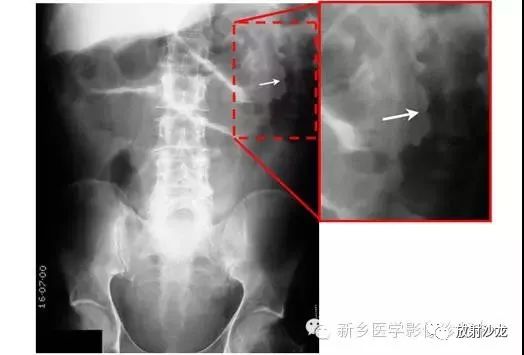

上图为一58岁男性,因1周前非特异性消化不良,行上消化道钡餐检查,做的腹部平片。患者最初表现为不确切的腹部不适和便血。现在又出现了腹痛和腹膜炎。箭头所指的典型表现是什么,诊断是什么?

箭头指向缺血穿孔性肠病患者的浅浮雕征。这也被称为双壁征或Rigler征。通常仅一侧肠壁可以看到。当双侧都能看到时,它表示腔内和腔外都有气体。当病人腹痛症状逐渐加重,肠壁穿孔是很有可能的。该患者手术过程中发现肠道脾曲缺血穿孔性肠病。